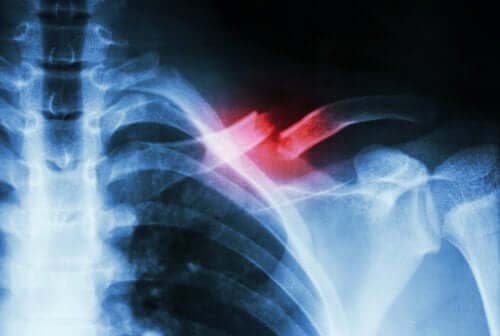

كسور الإجهاد – اكتشف معنا ما هي، أنواعها، والعظام التي تصيبها

من الصعب تشخيص هذا النوع من الكسور لأنها لا تظهر في الأشعة السينية. ولذلك يحتاج تشخيصها إلى طبيب متخصص وفحوصات معينة للتفرقة بينها وبين الحالات الطبية الأخرى.